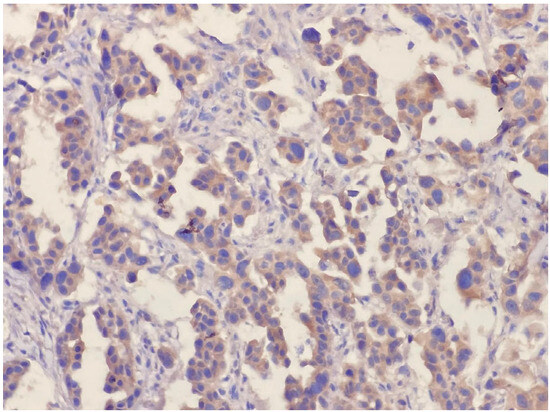

During HER-3 immunohistochemical staining evaluation, both positive and negative controls were taken into account. Staining in more than 30% of tumor cells was considered positive, consistent with the positivity threshold applied in previously published immunohistochemical studies evaluating HER3 expression in NSCLC [20,22]. Evaluation was based on membranous staining intensity. Weak membranous staining was scored as 1, complete but moderate membrane staining was scored as 2, and complete and strong staining was scored as 3 (Figure 1 and Figure 2). HER3 immunohistochemical evaluation was performed by two experienced pathologists with expertise in thoracic pathology at our center. The staining results were independently reviewed and scored according to predefined criteria, and any discrepancies were resolved by consensus. Formal interobserver agreement was not statistically assessed, which represents a limitation of the study.

Figure 2.

Cytoplasmic diffuse positive reaction (×200).